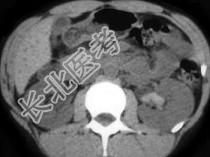

- 单项选择题该患者因血尿急诊,根据所提供图像, 最可能的诊断是 ( )

A、肾结石

B、血块

C、移行细胞癌

D、息肉

E、以上都不是